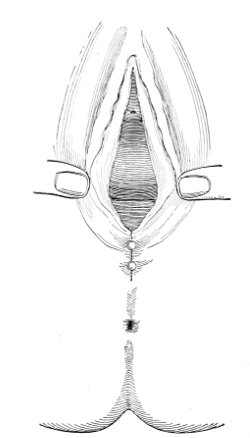

Slight Median laceration of the Perineum.—In this injury the tear takes place through the fourchette. Posteriorly it may extend as far as the sphincter ani muscle. Upward it may extend for an inch up the posterior vaginal wall. The appearance of this tear is shown in Fig. 33. It will be noted that, as this tear takes place in the median line, none of the muscles that support the perineum are involved, nor are the planes of fascia injured. The perineum is slightly split, and the insertions and origins of the muscles and the fascia are slightly separated. The supporting structures of the perineum and the pelvic floor are, however, uninjured.

Fig. 33.—Recent slight median laceration of the perineum: sutures introduced.

If this tear is detected after labor, it should be closed by the immediate operation. A slight tear involving chiefly the cutaneous aspect of the perineum should be closed by three or four sutures introduced from the outside, as in Fig. 33. The needle should be introduced about a quarter of an inch from the edge of the wound. It should not be passed parallel with the plane of the lacerated surface, but should be swept outward and then inward toward the 68 angle at the bottom of the tear (Fig. 34). It may either emerge at the angle and be re-introduced, or it may be passed directly through to the skin-margin on the opposite side of the wound. If the suture is passed in this way, there will be perfect apposition throughout the whole surface of laceration. If the sutures are improperly passed, there may result only apposition of the skin-edges.

Fig. 34.—Diagram representing the correct and the incorrect method of passing the suture for closure of slight perineal laceration.

If the laceration extends up the posterior vaginal wall, two sets of sutures must be introduced—one on the vaginal aspect of the tear, and one on the skin aspect (Fig. 35).